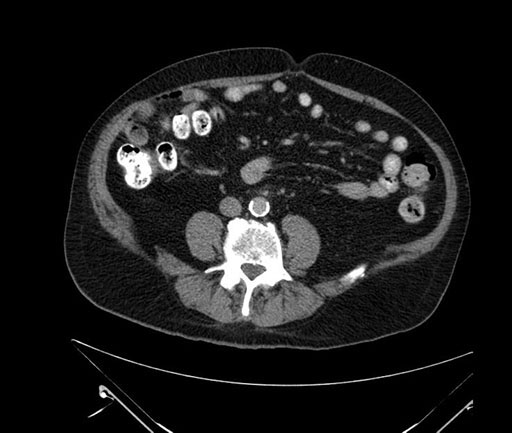

Imaging Analysis

Look through the patient's CT scan to identify any areas of concern for the necessary procedure.

Based on your CT findings, which issue(s) would give reason for "planned slowing down moment(s)" in this case?

Considering a standard Whipple procedure, what step(s) of the operation would you do differently in this case?